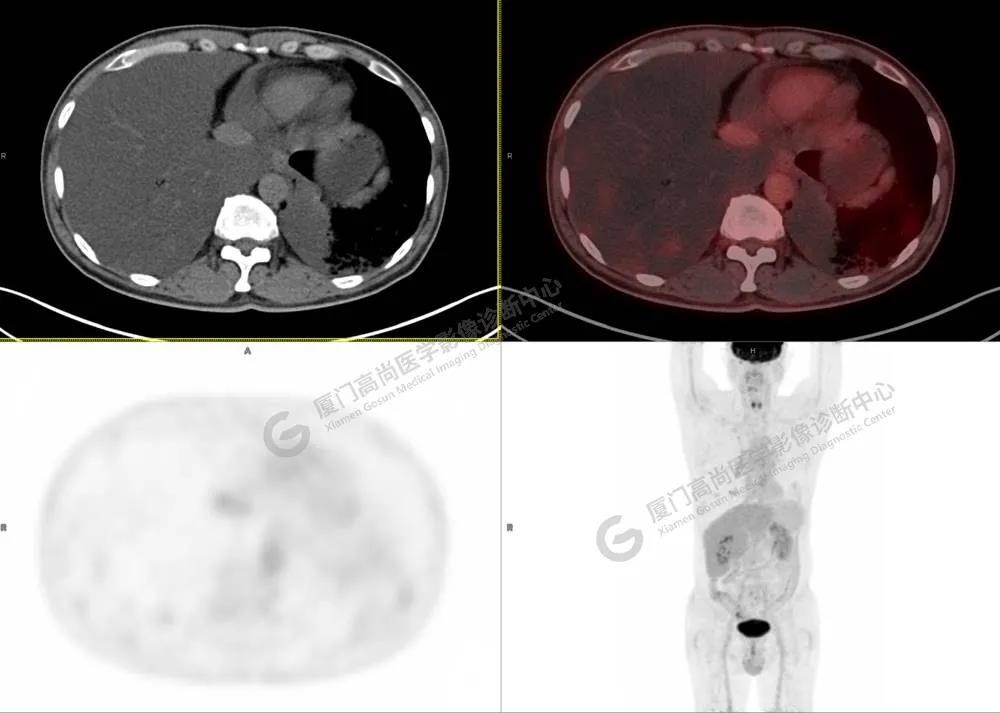

PET/CT影像圖

圖3

PET/CT所見:雙肺大片實(shí)變影及磨玻璃影,部分呈地圖樣改變,累及右肺尖,部分放射性攝取輕微增高,SUVmax 1.77,其內(nèi)見多發(fā)支氣管充氣征象。

影像診斷: 雙肺大片實(shí)變影及磨玻璃影,大部分代謝不高,局部代謝輕微增高,考慮肺泡蛋白沉積癥,建議病理學(xué)檢查或肺泡灌洗物檢查。